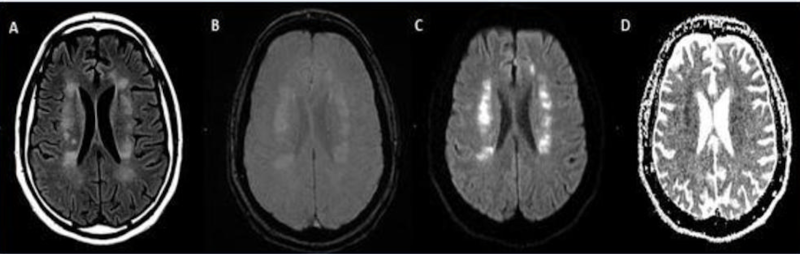

Stroke seen in a 41-year-old male patient with COVID-19 infection. Image courtesy of RSNA

-

Acute anterior cerebral artery/middle cerebral artery watershed infarction seen in a 47-year-old male patient who presented with COVID-19 pneumonia. Image courtesy of RSNA

A 62-year-old male with a past medical history of hypertension presenting with seizures. Image courtesy of RSNA

A 56-year-old male patient with diabetes and hypertension who presented with complaints of confusion. Courtesy of RSNA